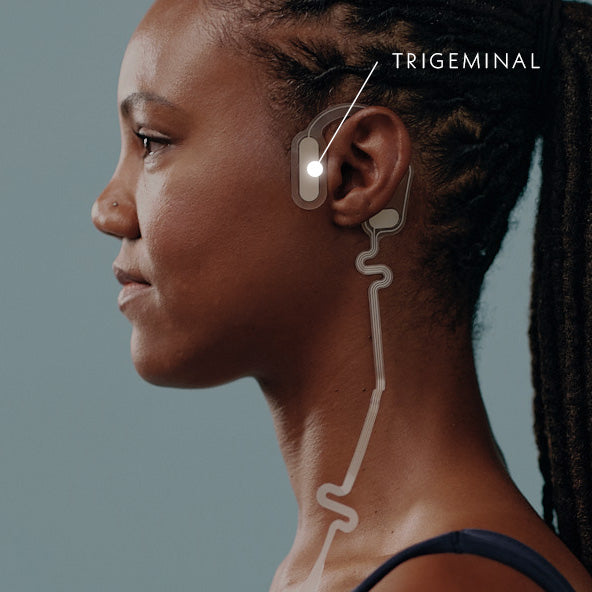

Neurostimulation engages pathways involved in autonomic regulation. By stimulating external branches of the vagus and trigeminal nerves, it supports a shift away from elevated sympathetic activation and toward greater parasympathetic balance.²

The Trigeminal Nerve

The Sensory PathwayThe trigeminal nerve is one of the primary sensory nerves of the head and face. It plays a central role in how the brain interprets physical sensations, including signals related to comfort and discomfort.

Trigeminal pathways also connect to brain regions involved in neurochemical signaling, the brain’s internal messaging system. These pathways influence naturally occurring compounds such as endorphins (i.e. body’s natural pain killers) and other regulatory messengers, helping explain their relevance to comfort and overall well-being during the menstrual cycle.